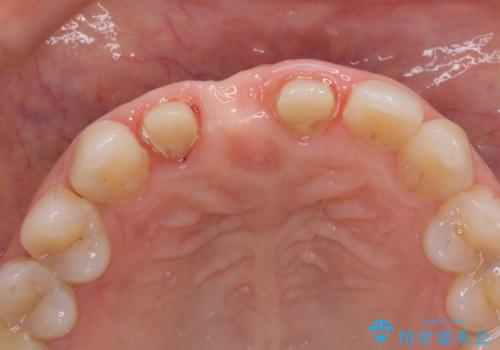

現在装着されているブリッジを除去したところ、歯ぐきよりも上に存在する歯質(縁上歯質)が少なく、土台の形態の悪さや不適合などさまざまな問題があります。

根管治療を行ったのち、歯周外科を行うことで、欠損部の歯ぐきの厚みを出し、縁上歯質を獲得することで、長期的な予後の見込めるブリッジを製作できる環境を整備していきます。